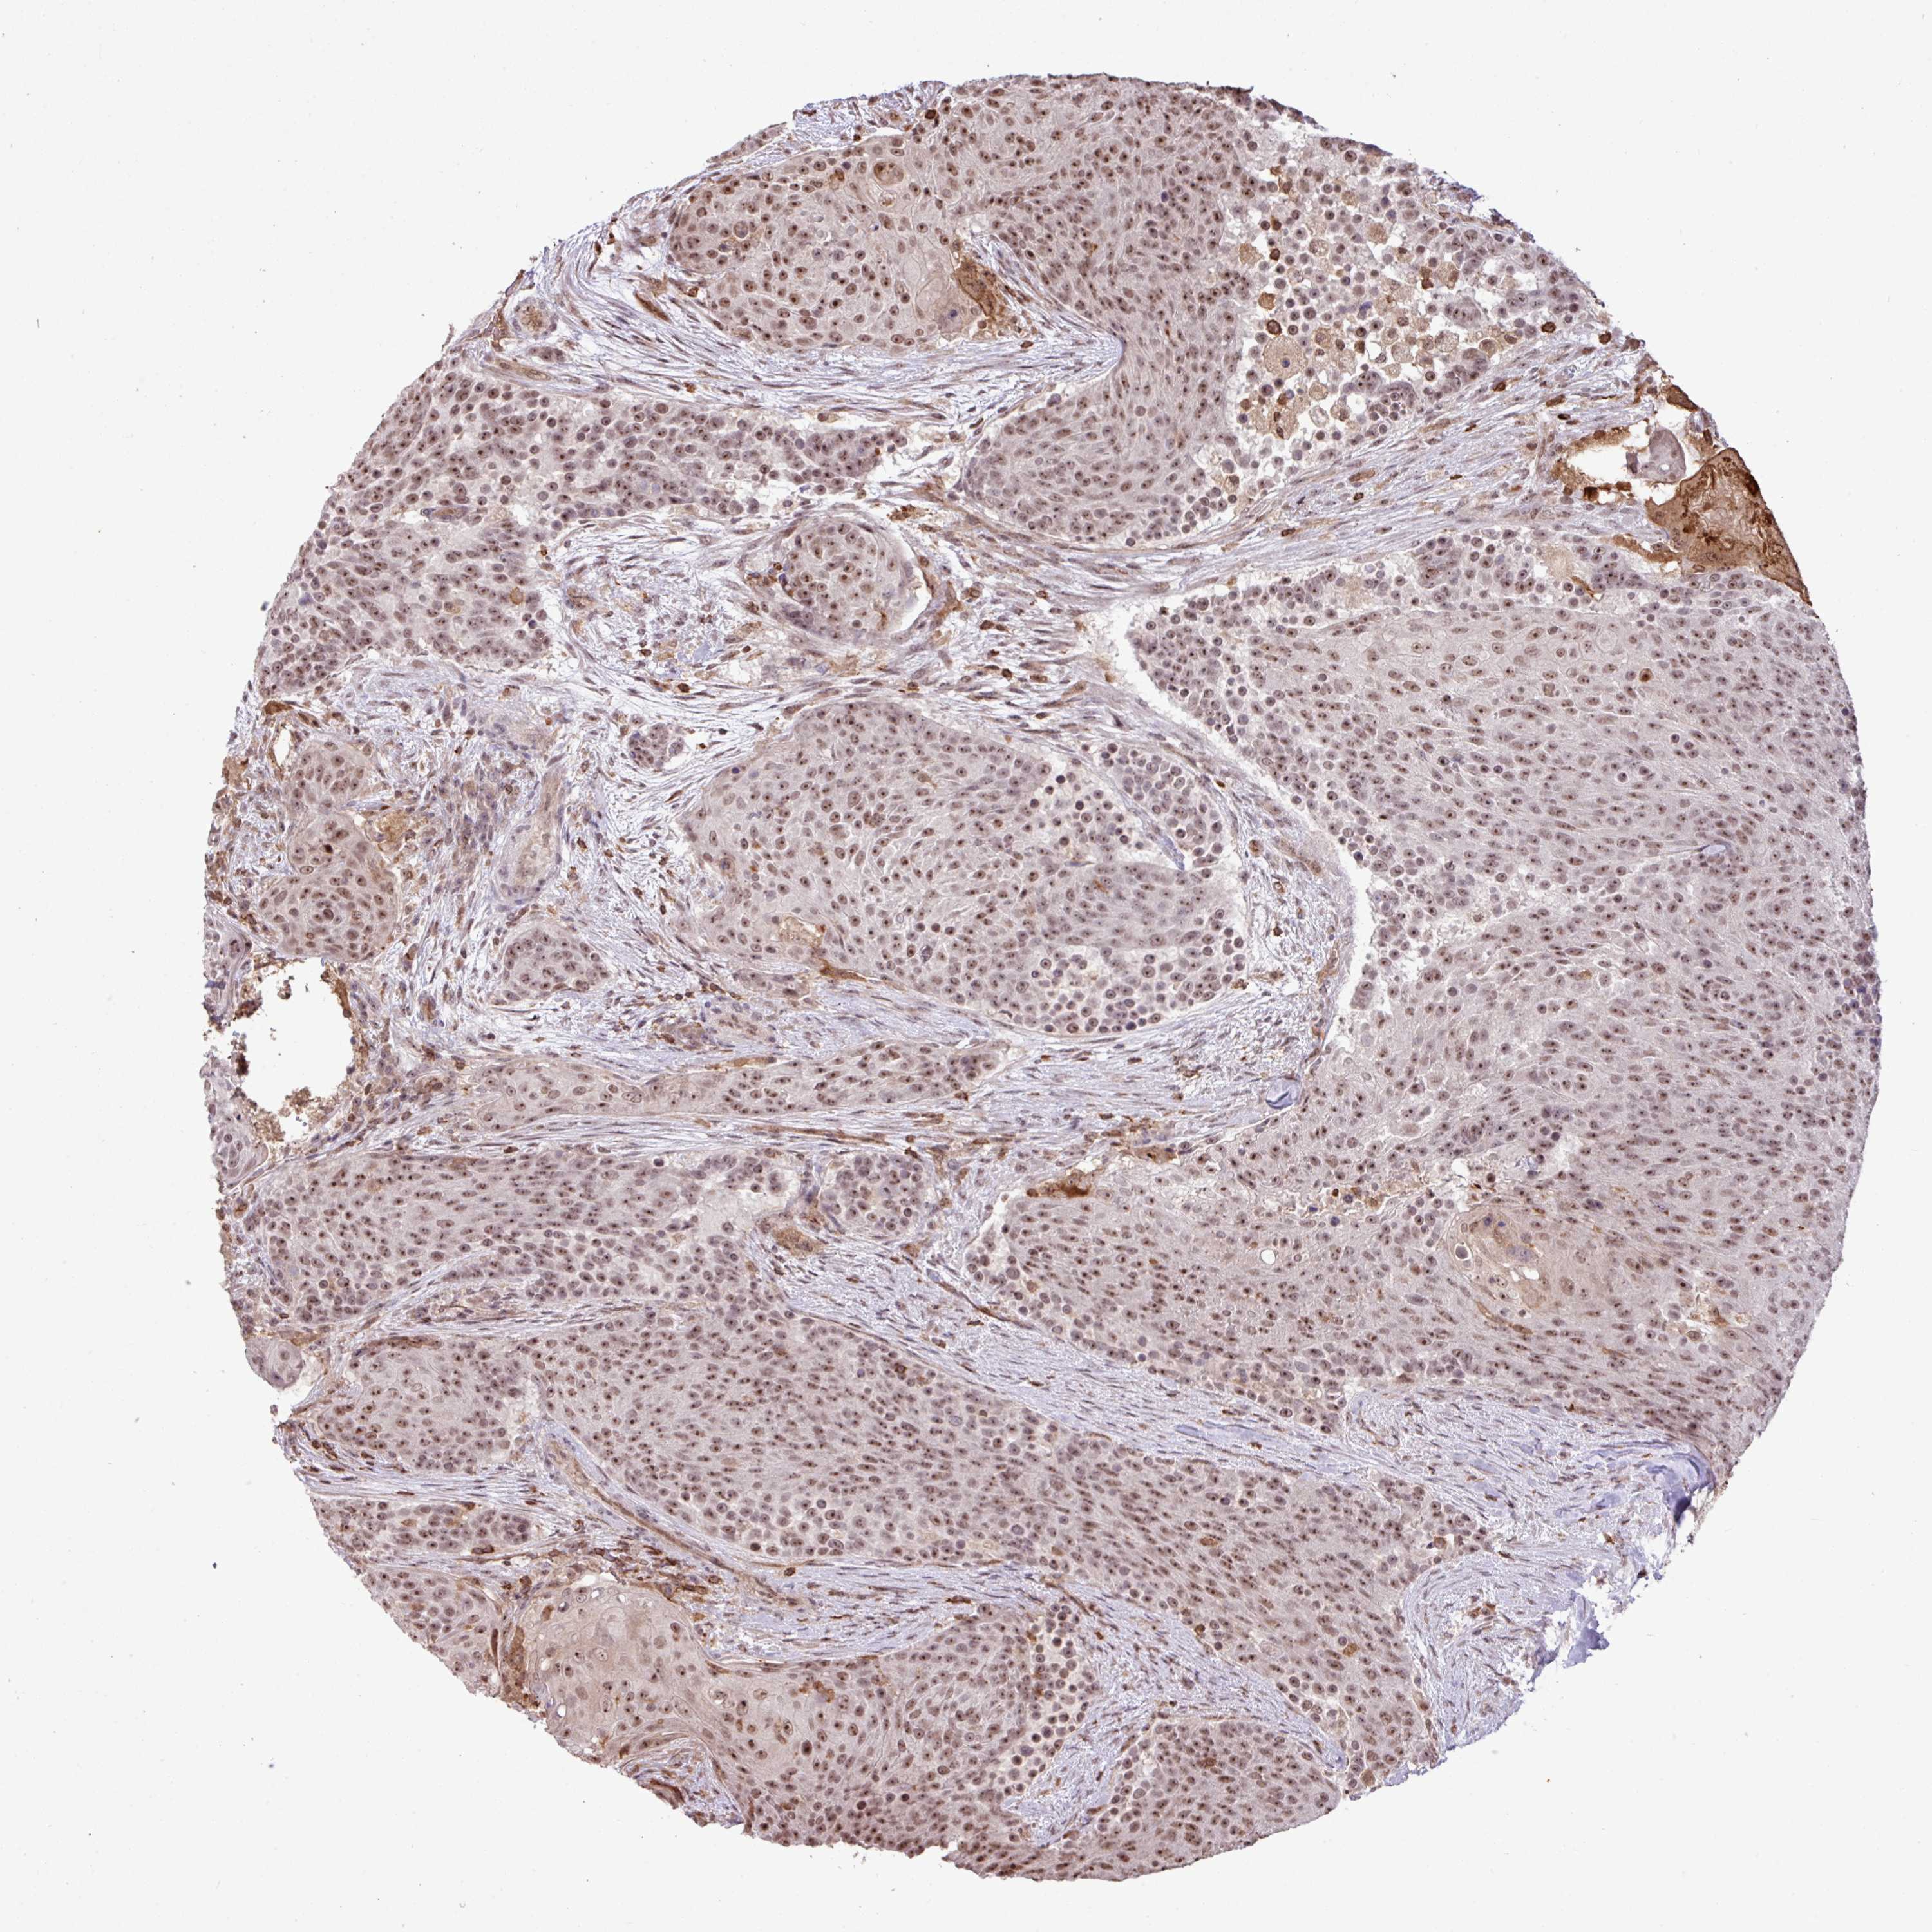

UROTHELIAL CANCER - Protein expressioni

A mouse-over function shows sample information and annotation data. Click on an image to view it in a full screen mode. Samples can be filtered based on level of antibody staining by selecting one or several of the following categories: high, medium, low and not detected. The assay and annotation is described here.

Note that samples used for immunohistochemistry by the Human Protein Atlas do not correspond to samples in the TCGA dataset.

Antibody stainingi

Antibody staining in the annotated cell types in the current human tissue is reported as not detected, low, medium, or high, based on conventional immunohistochemistry profiling in selected tissues. This score is based on the combination of the staining intensity and fraction of stained cells.

Each image is clickable and will lead to virtual microscopy that enables deeper exploration of all samples and also displays staining intensity scores, fraction scores and subcellular localization as well as patient and tissue information for each sample.

Antibody HPA051832

Staining

High

Medium

Low

Not detected

Intensity

Strong

Moderate

Weak

Negative

Quantity

>75%

75%-25%

<25%

None

Location

Nuclear

Cytoplasmic/membranous

Cytoplasmic/membranous,nuclear

Urothelial carcinoma, High grade

Urothelial carcinoma, Low grade

Urothelial carcinoma, NOS